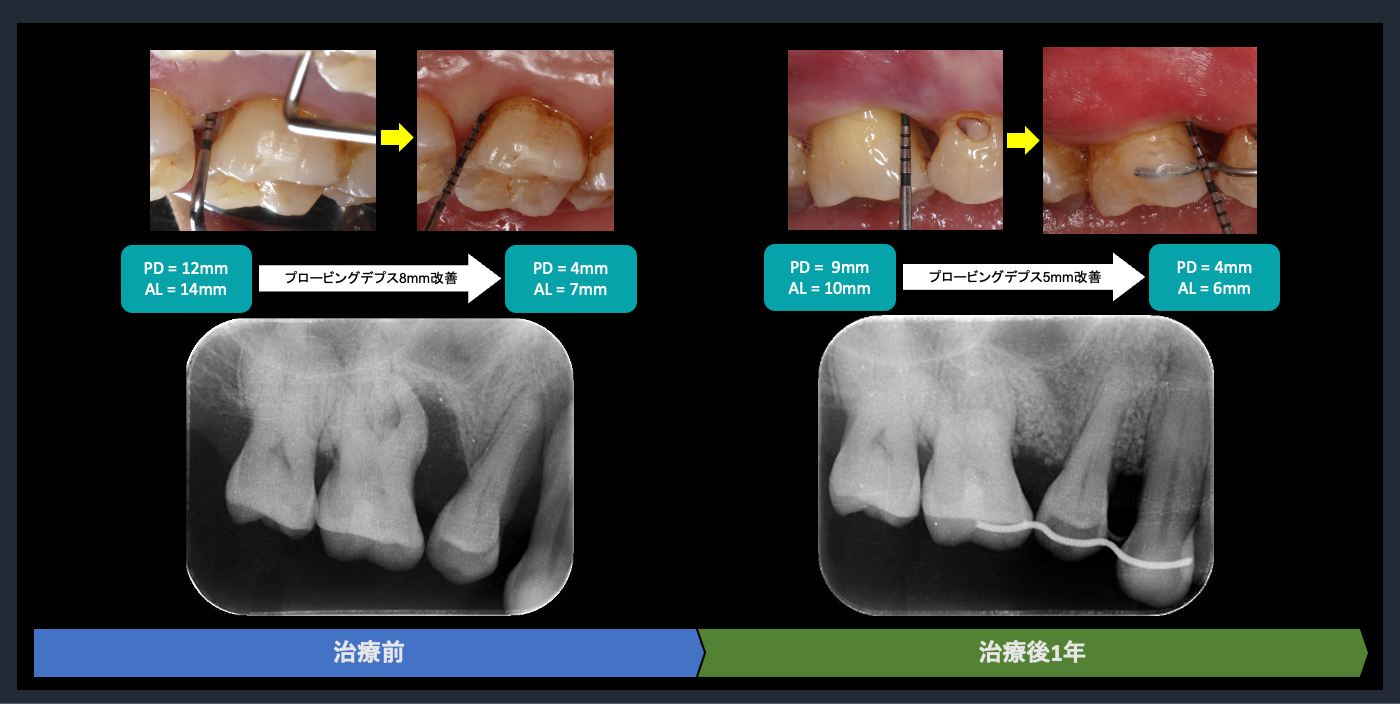

| 概要 | 歯周病が進行しており、右上臼歯部に重度の骨吸収像が認められます。失われた骨を再生し、歯の生存率を高めることを目的に、再生療法を試みました。良好な結果を得ることができました。問題なく使っていただいております。 再生療法を行う利点としては、ポケットが浅くなるので、患者様ご自身でのブラッシングで管理し、コントロールすることが可能になります。もちろん定期的なメインテナンスは必要不可欠です。 |

歯周組織再生療法の評価

Post-treatment evaluation

Post-treatment evaluation

歯周組織再生療法の評価

Post-treatment evaluation

Post-treatment evaluation

歯周組織再生療法の評価

Post-treatment evaluation

Post-treatment evaluation

歯周組織再生療法の評価

Post-treatment evaluation

Post-treatment evaluation

歯周組織再生療法の評価

Post-treatment evaluation

Post-treatment evaluation

歯周組織再生療法の評価

Post-treatment evaluation

Post-treatment evaluation

歯周組織再生療法の評価

Post-treatment evaluation

Post-treatment evaluation